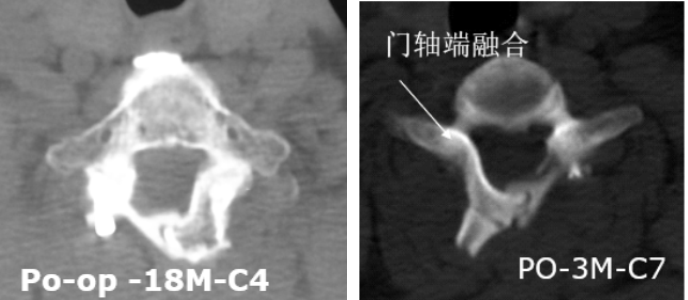

3.有效防止術(shù)后再關(guān)門,為脊髓提供強力保護

4.可融合,遠期穩(wěn)定性好